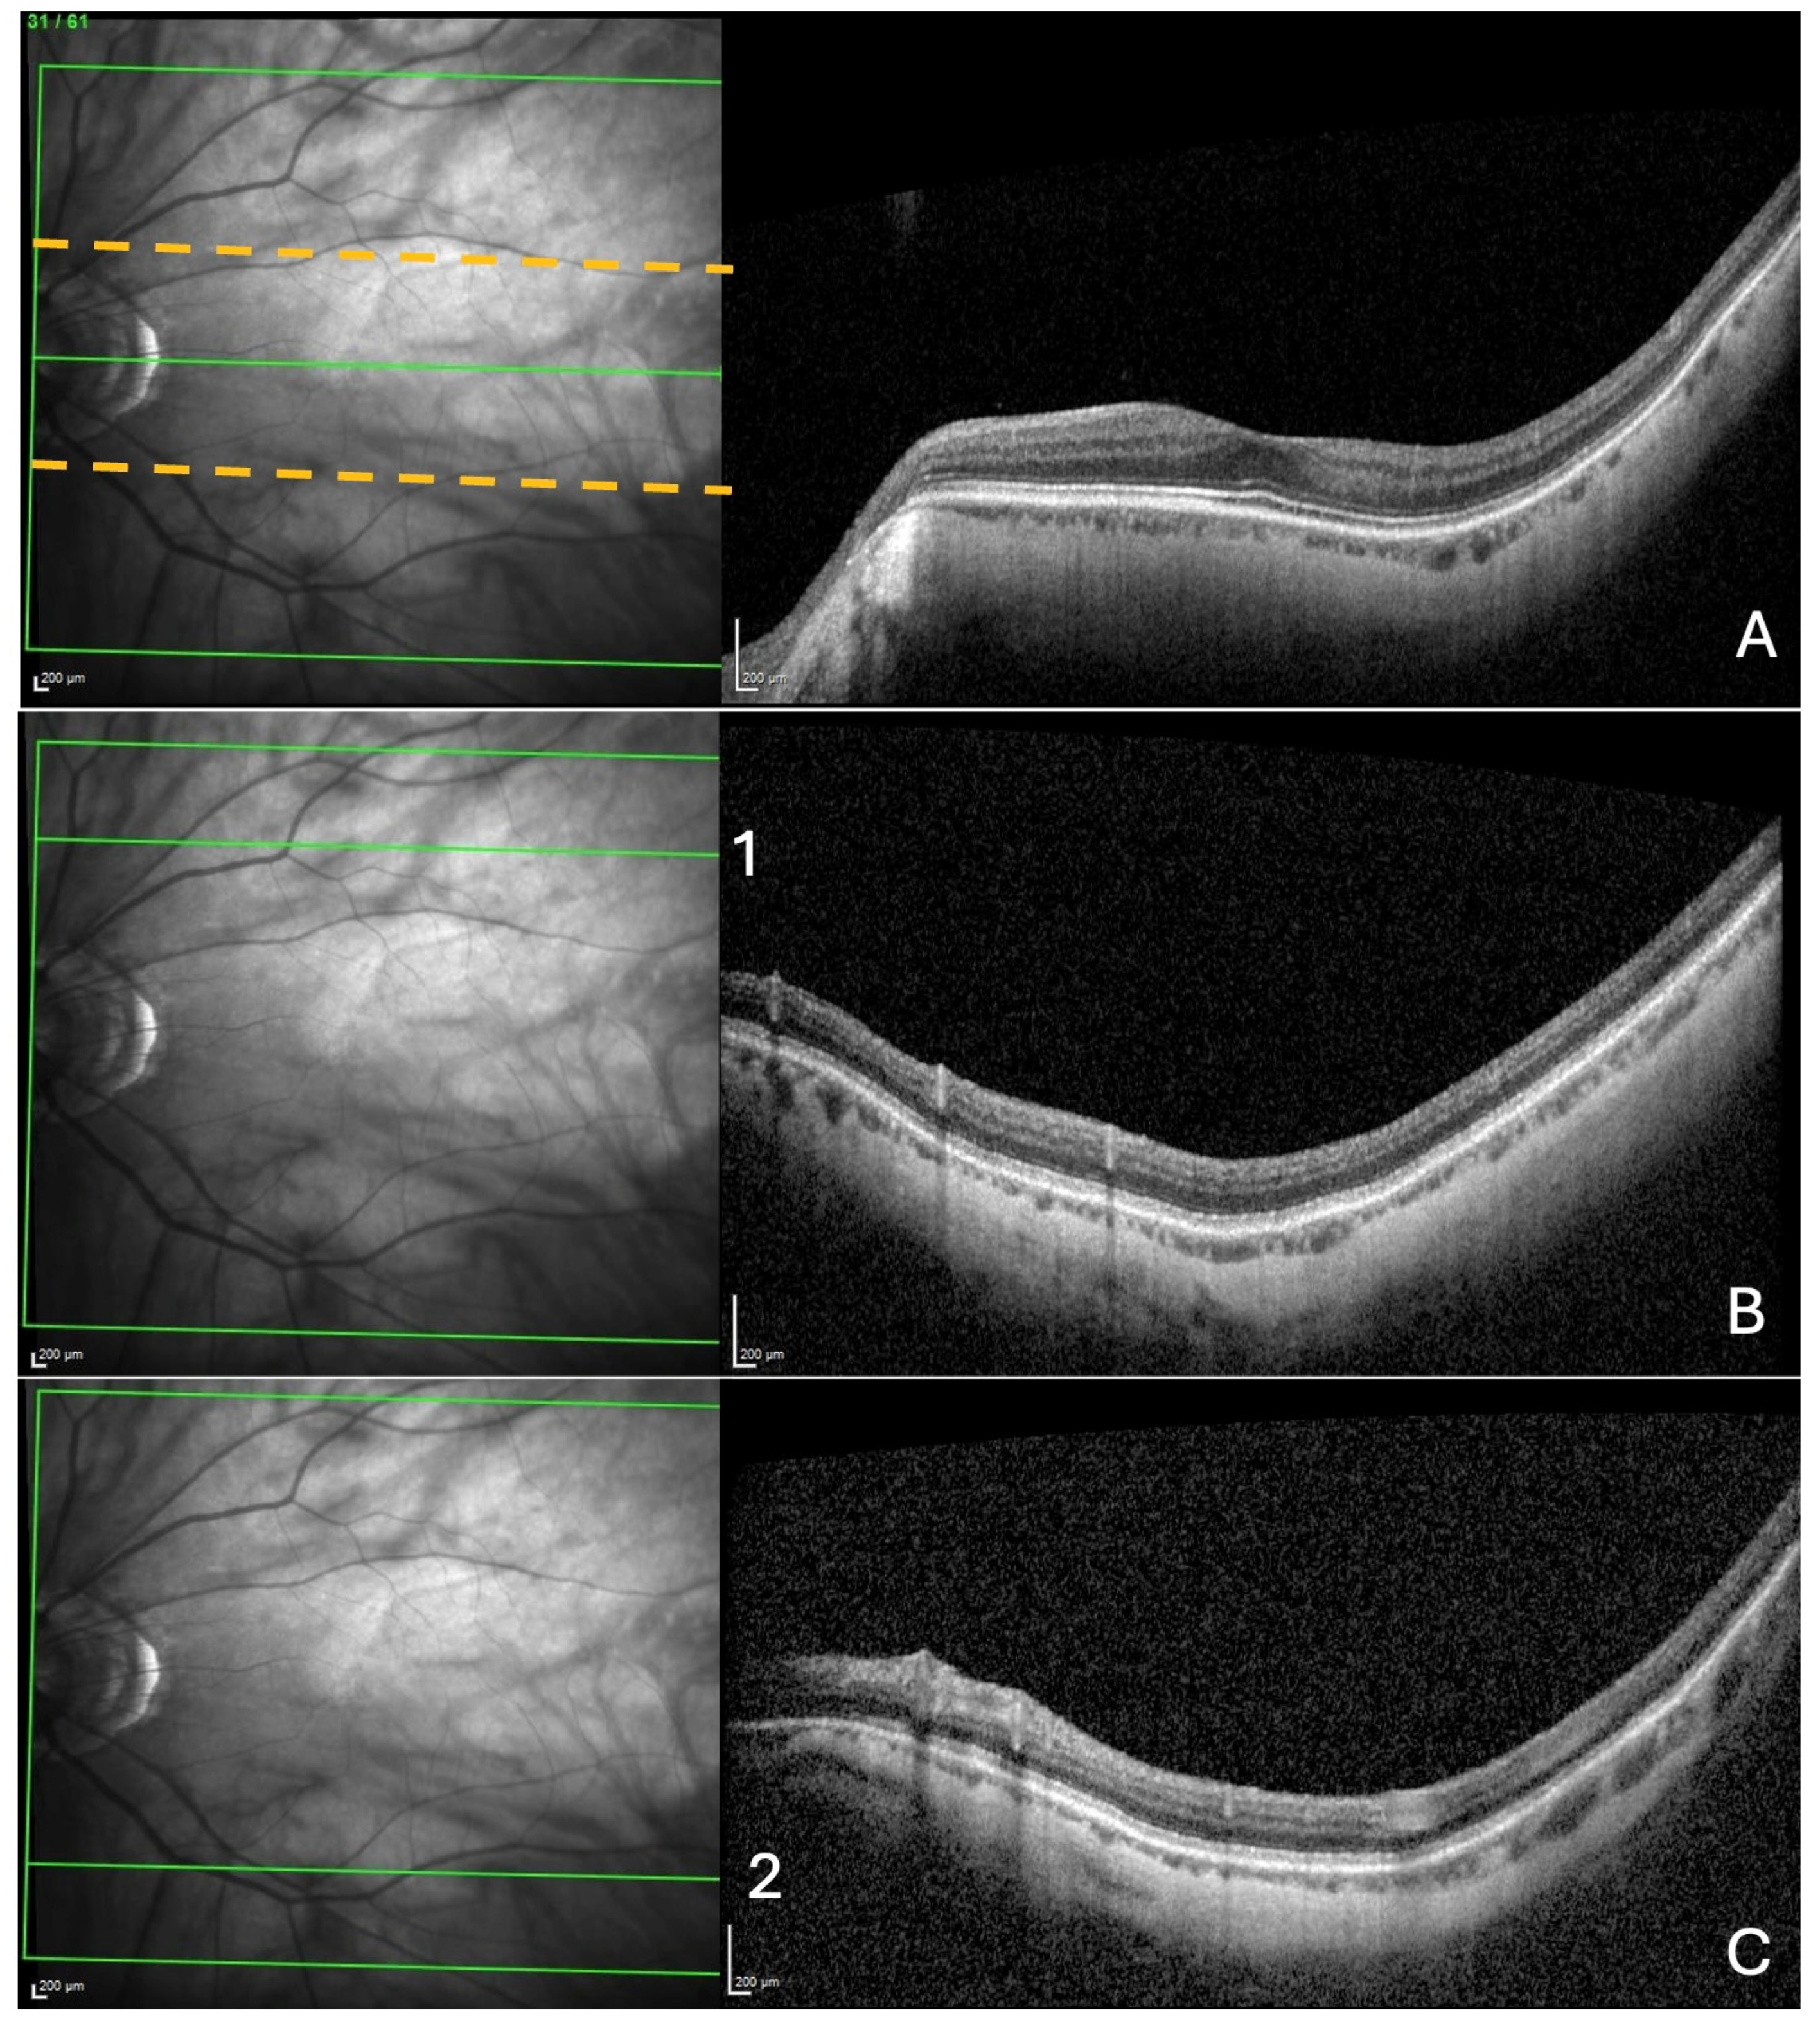

- A search for choroidal thinning in 3 locations in the temporal part of the posterior pole.

- Measurement of the choroidal thinning and distance from fovea to thinning.